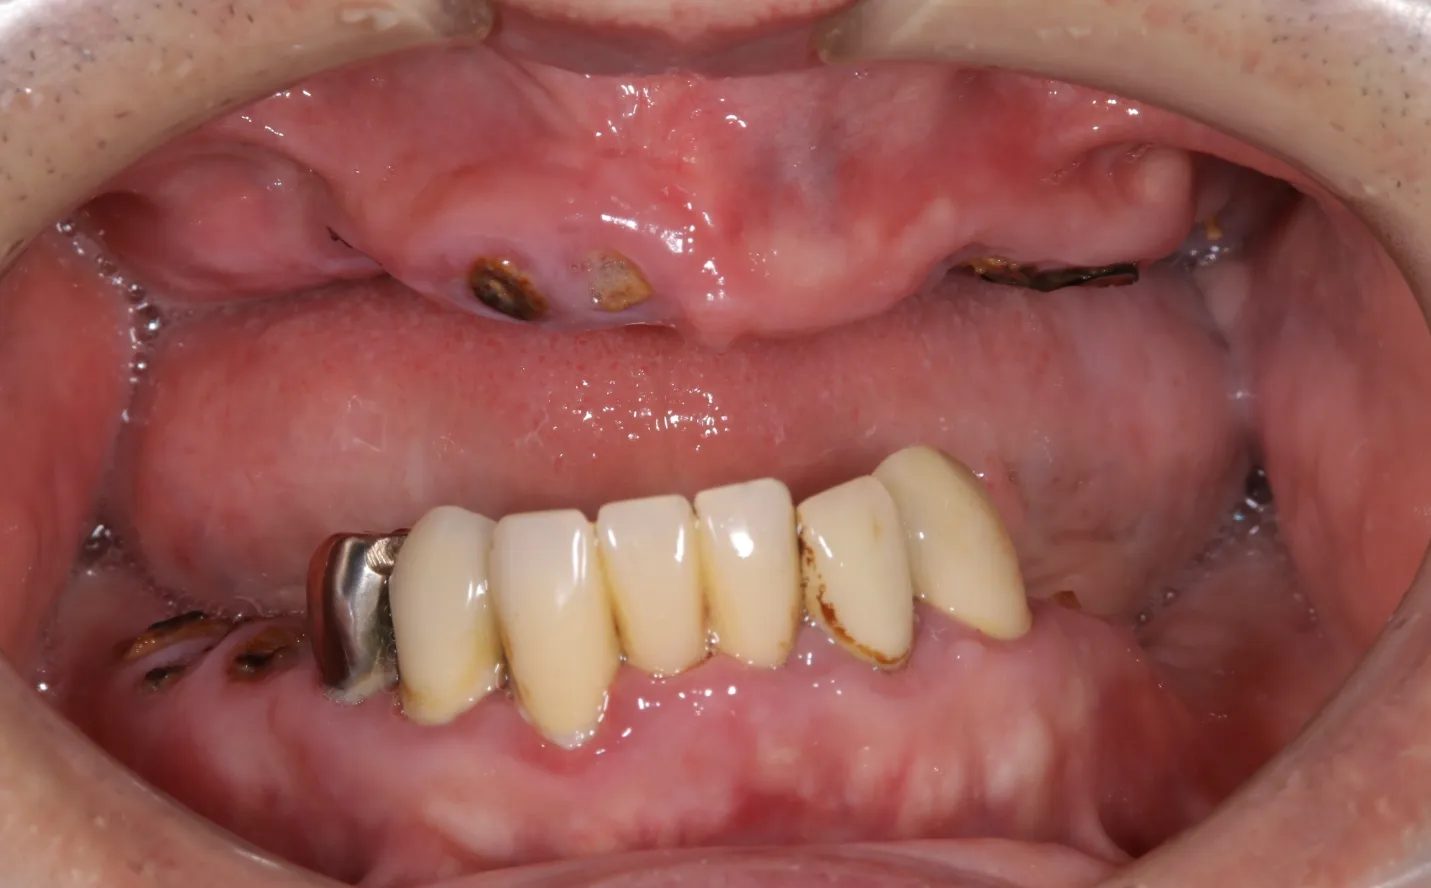

【症例1】

主訴

噛めない。不自由なく食事をしたい。

年齢・性別

50代男性

治療内容

上下顎フルインプラント

期間

1年2ヶ月

費用

7,279,000円